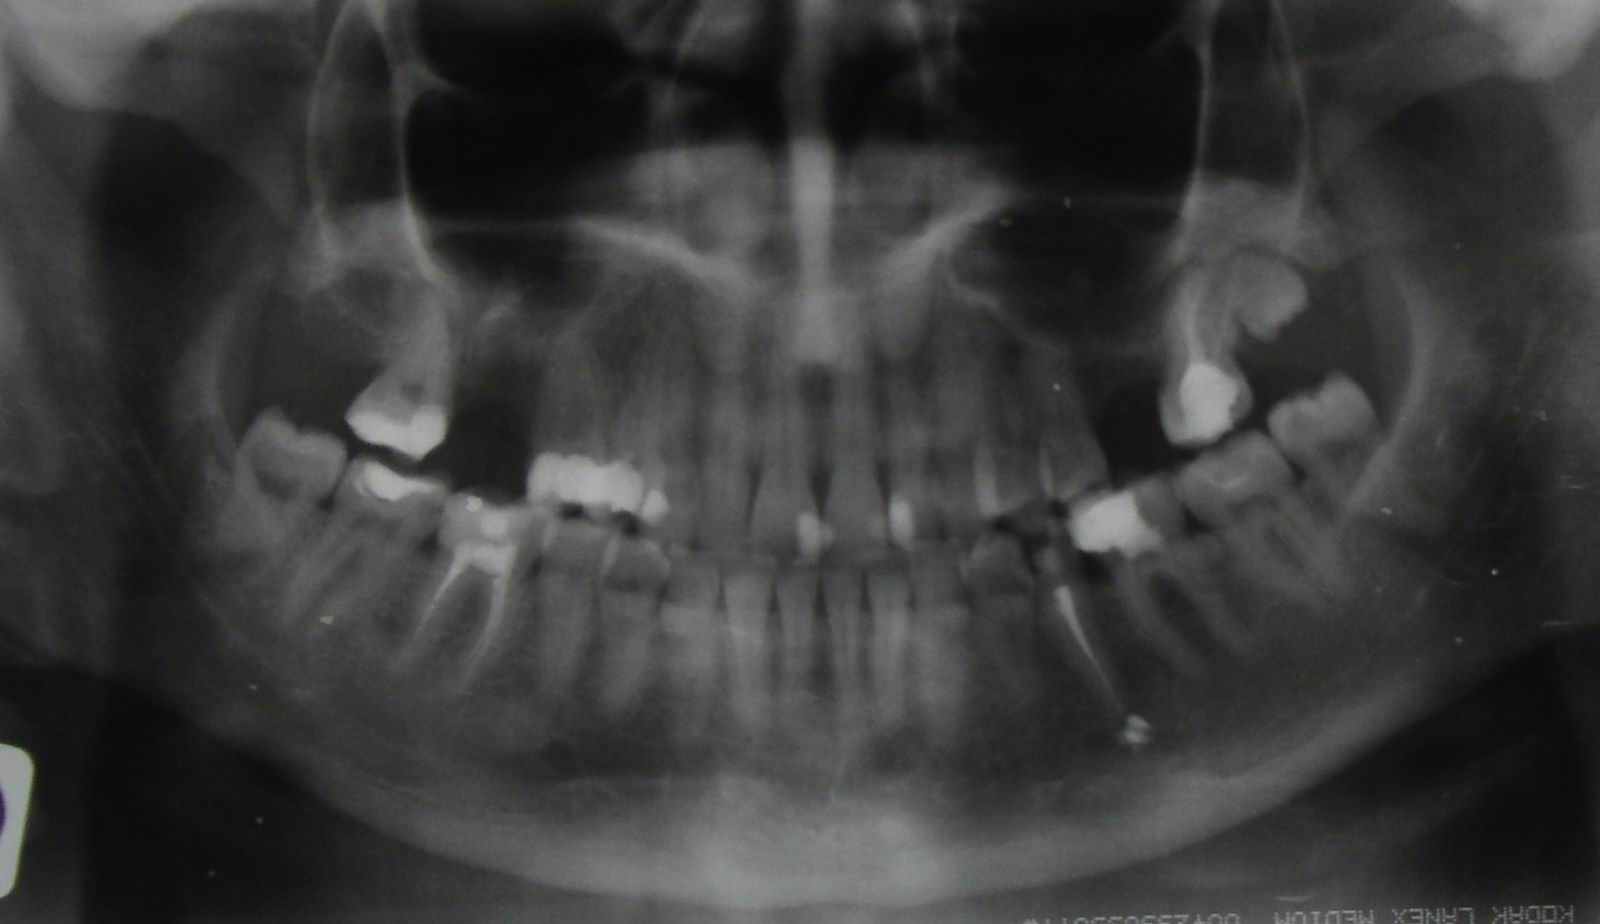

ВИЗУАЛИЗИРОВАННЫЕ ТЕСТОВЫЕ ЗАДАНИЯ

![]() | 004. ПО ДАННЫМ РЕНТГЕНОВСКОЙ КОМПЬЮТЕРНОЙ ТОМОГРАФИИ МОЖНО ПОСТАВИТЬ ДИАГНОЗ

![]() ![]() | 006. Причиной невропатии ветви тройничного нерва в данном случае является

![]() | 012.Предварительный диагноз у данного больного